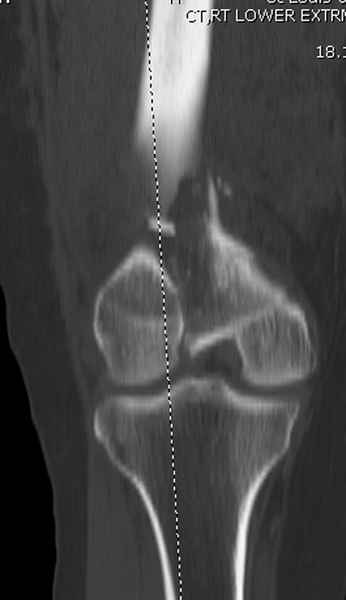

Мы бы не стали открывать, такие переломы срастаются, хотя бы и с краевым дефектом. То есть если удалять стержень потом, то сильно попозже обычного. В приложении пример. Сразу после операции и через 11 мес. Понятное дело, пациент к тому времени давно и не хромал, и функция колена была полная.

Приветствую всех коллег!!Во первых слева хотелось бы видеть четкую боковую проекцию а лучше КТ. По р-мам есть сомнения насчет повреждения суставной поверхности. При подобных переломах даже внутрисуставных без смещения хорошие результаты показал закрытый ретроградный остеосинтез универсальным бедренным стержнем Деост.Кстати при внутрисуставном переломе возможно применение вместо винтов стягивающих болтов!!(См. метод.Деост).При переломе справа также стержень Деост. Однако без открытия Вам не удастся устранить интерпозицию, только промучаетесь!Из минимального разреза удалите интерпозициб и фиксируйте стержнем. Причем универсальный стежень Деост позволяет фиксировать дистально минимум на трех уровнях!